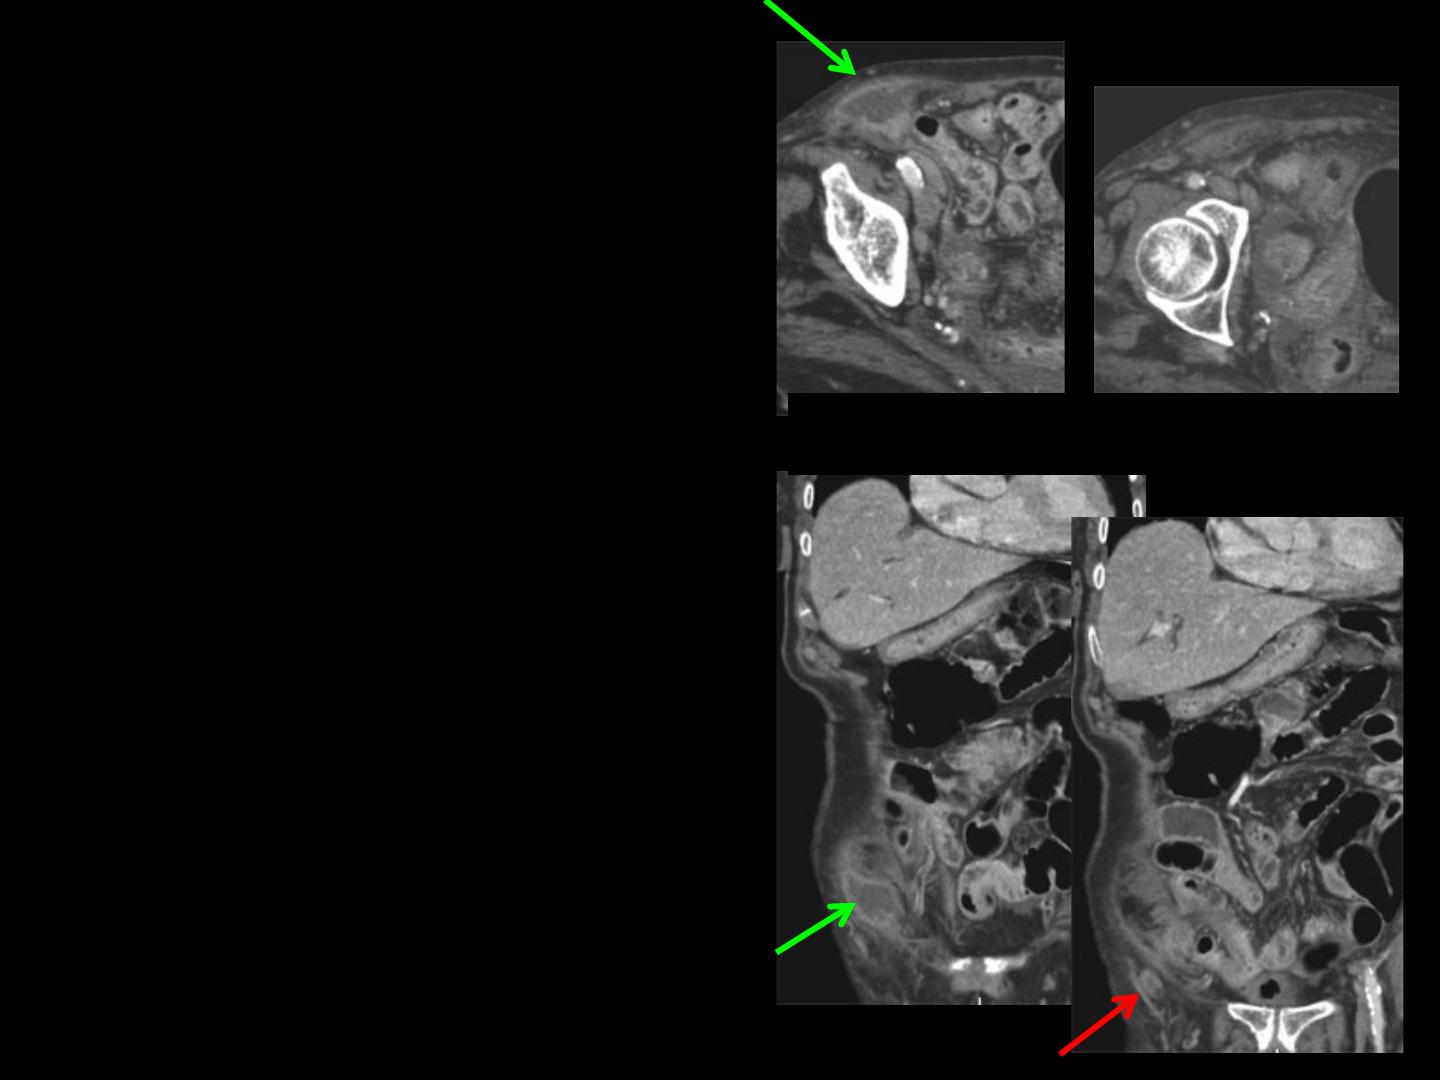

-autre cas de hernie de

Claudius Amyand .

L'appendice est bien visible

dans le sac herniaire ; il n'est

le siège d'aucun signe

inflammatoire